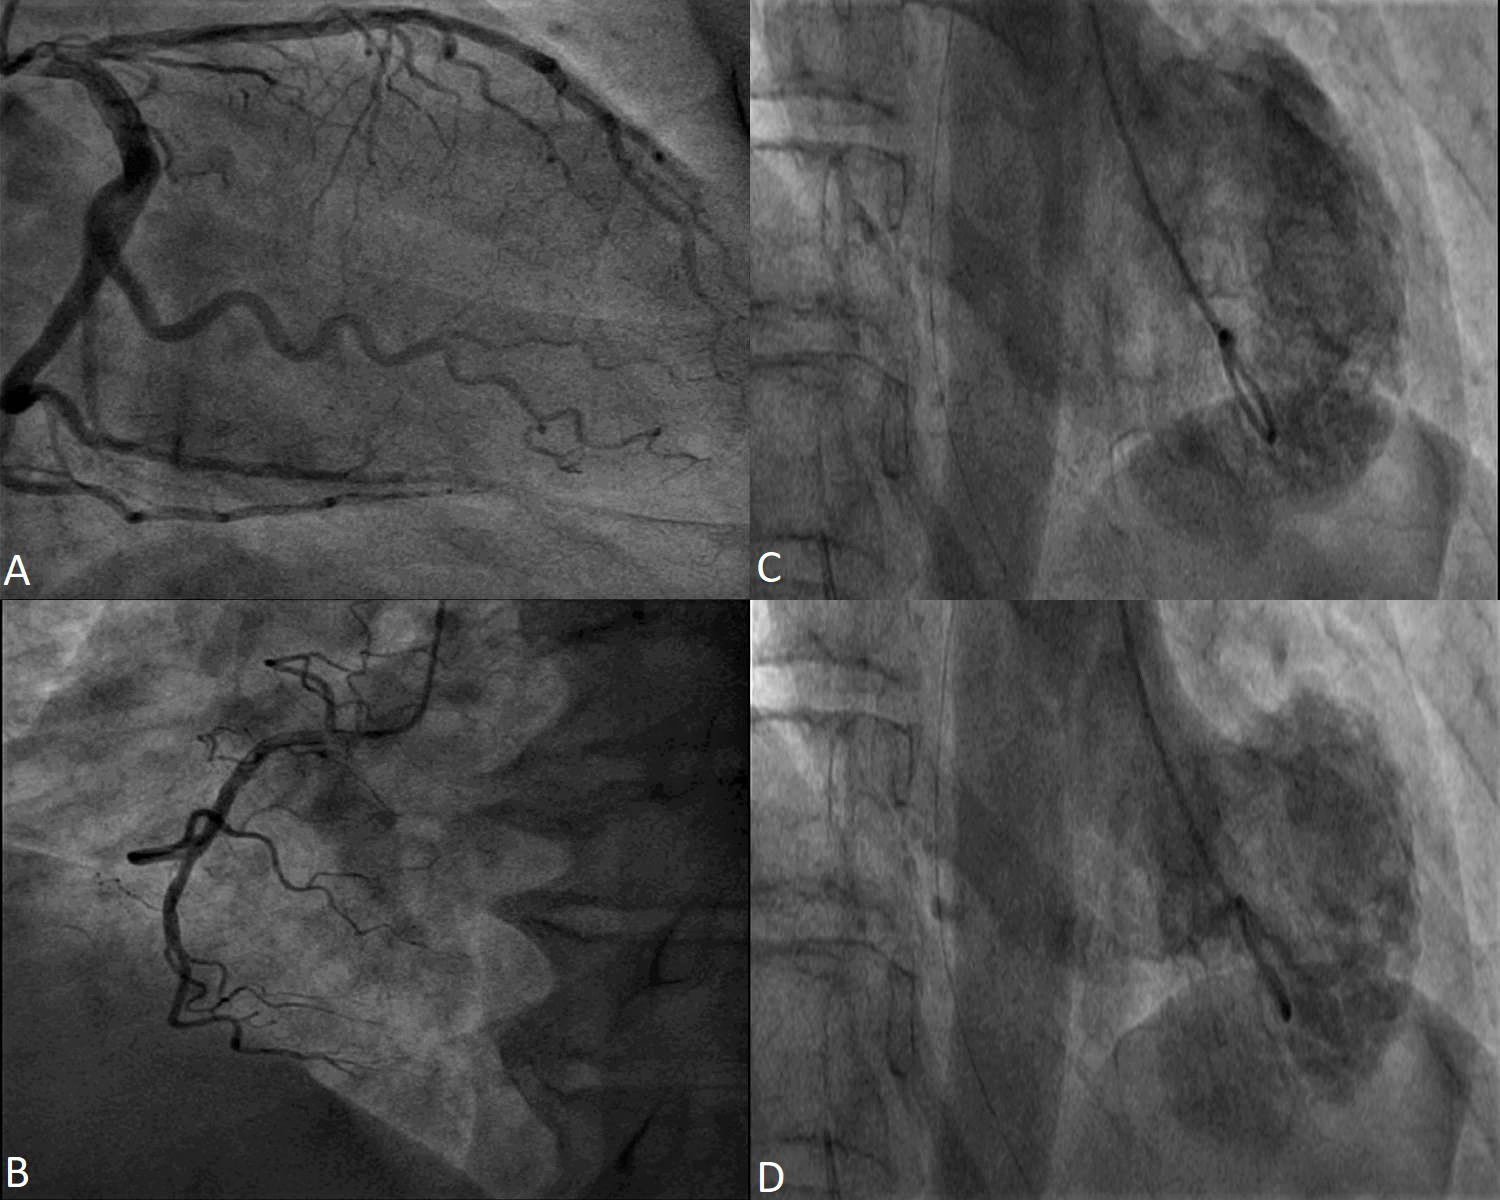

Since the most frequent clinical presentation of a TS case is that of an acute coronary syndrome with ST segment elevation, the main investigation is coronary angiography in order to exclude a type 1 myocardial infarction [23, 24]. Coronary arteries need to be carefully assessed, in several angiographic views. Usually, patients with TS have non obstructive epicardial coronary arteries but coronary disease unrelated to the motion anomaly of the LV may be present. However, coronary artery disease is not an exclusion criteria [25]. The main reason is that the regional wall motion abnormalities (RWMA) extend beyond the vascularization of a single coronary artery [26]. Even if the patient has coronary artery disease, it is not an exclusion criteria if the depending myocardial territory is not concordant with the wall motion abnormalities [27, 28]. When coronary artery disease is found, orthogonal angiographic views of the artery and LV ventriculography help in observing the mismatch between the coronary stenosis and the wall motion abnormality. The “apical nipple sign” was described on ventriculography images: a small zone, right at the LV apex, with preserved contractility, found in approximately 30% of TS patients with apical pattern. This sign was not described in patients with acute anterior myocardial infarction and may help in differentiating the two conditions [29].

Most of the time, TS diagnosis is associated with angiographically normal or non-obstructive coronary arteries [30] (Fig. 1). In patients diagnosed with TS and coronary artery disease, intracoronary imaging techniques, like intravascular ultrasound and optical coherence tomography, revealed that coronary plaques had no sign of thrombosis, erosion or dissection [31, 32, 33, 34].

Fig. 1.Coronary angiography in a 53 year-old female patient with Takotsubo Syndrome. Non-obstructive epicardial coronary arteries - images (A) and (B). Ventriculography showing apical akinesia and basal hyperkinesia - images (C) and (D).

In a lot of 11 consecutive patients admitted with acute coronary syndrome but later diagnosed with TS, the wall motion abnormalities were evaluated through ventriculography [35]. Unfortunately, the diagnostic workup did not include cardiac magnetic resonance (CMR) or patient follow-up after hospitalization. Even though ventriculography is a valuable tool in evaluating the circumferential pattern of ventricular motion abnormality when coronary angiography is performed, its usefulness is limited to the acute setting. Thus, in order to prove the reversible nature of the systolic dysfunction another imaging method, usually echocardiography, needs to be performed. In a retrospective study of 20 patients with TS, LV contractility was compared by assessing ventriculograms and strain derived echocardiography. The results suggest that echocardiography and strain analysis is the preferred modality in assessing the LV contractility [36].